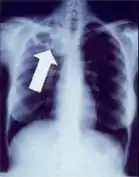

Chest X-ray

Tuberculosis creates cavities visible in x-rays like this one in the patient's right upper lobe.

A posterior-anterior (PA) chest X-ray is the standard view used; other views (lateral or lordotic) or CT scans may be necessary.